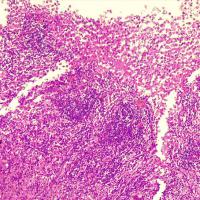

*Case 3 : Pr Modupeola Samaila/ Dr Rimamscep Ifusumu

email: mamak97@yahoo.com

Clinical detail: Female, 38 years. Orbital cystic tumour of 2 years duration.

Clinical diagnosis is orbital tumour query mucormycosis.

Please, consult the virtual slides of Case 3 below.